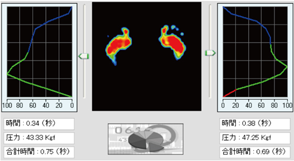

平衡機能検査

静止立位状態での重心動揺軌跡を動画で記録する事ができます。

重心動揺検査

重心の動揺奇跡を動画で経過観察や記録ができます。

動画で記録出来る事により、重心動揺計以外の用途にも使用でき、各機能訓練の現場でも経過観察に活用できます。

グラフ

重心線の軌跡をグラフ化し分析します。

主な検査項目 D250 平衡機能検査

重心動揺計 250点

○外周面積・矩形面積・実行値面積

○総軌跡長・単位軌跡長・単位面積軌跡長

○動揺中心変位

○ロンベルグ率

○めまい・平衡障害や機能回復訓練の評価